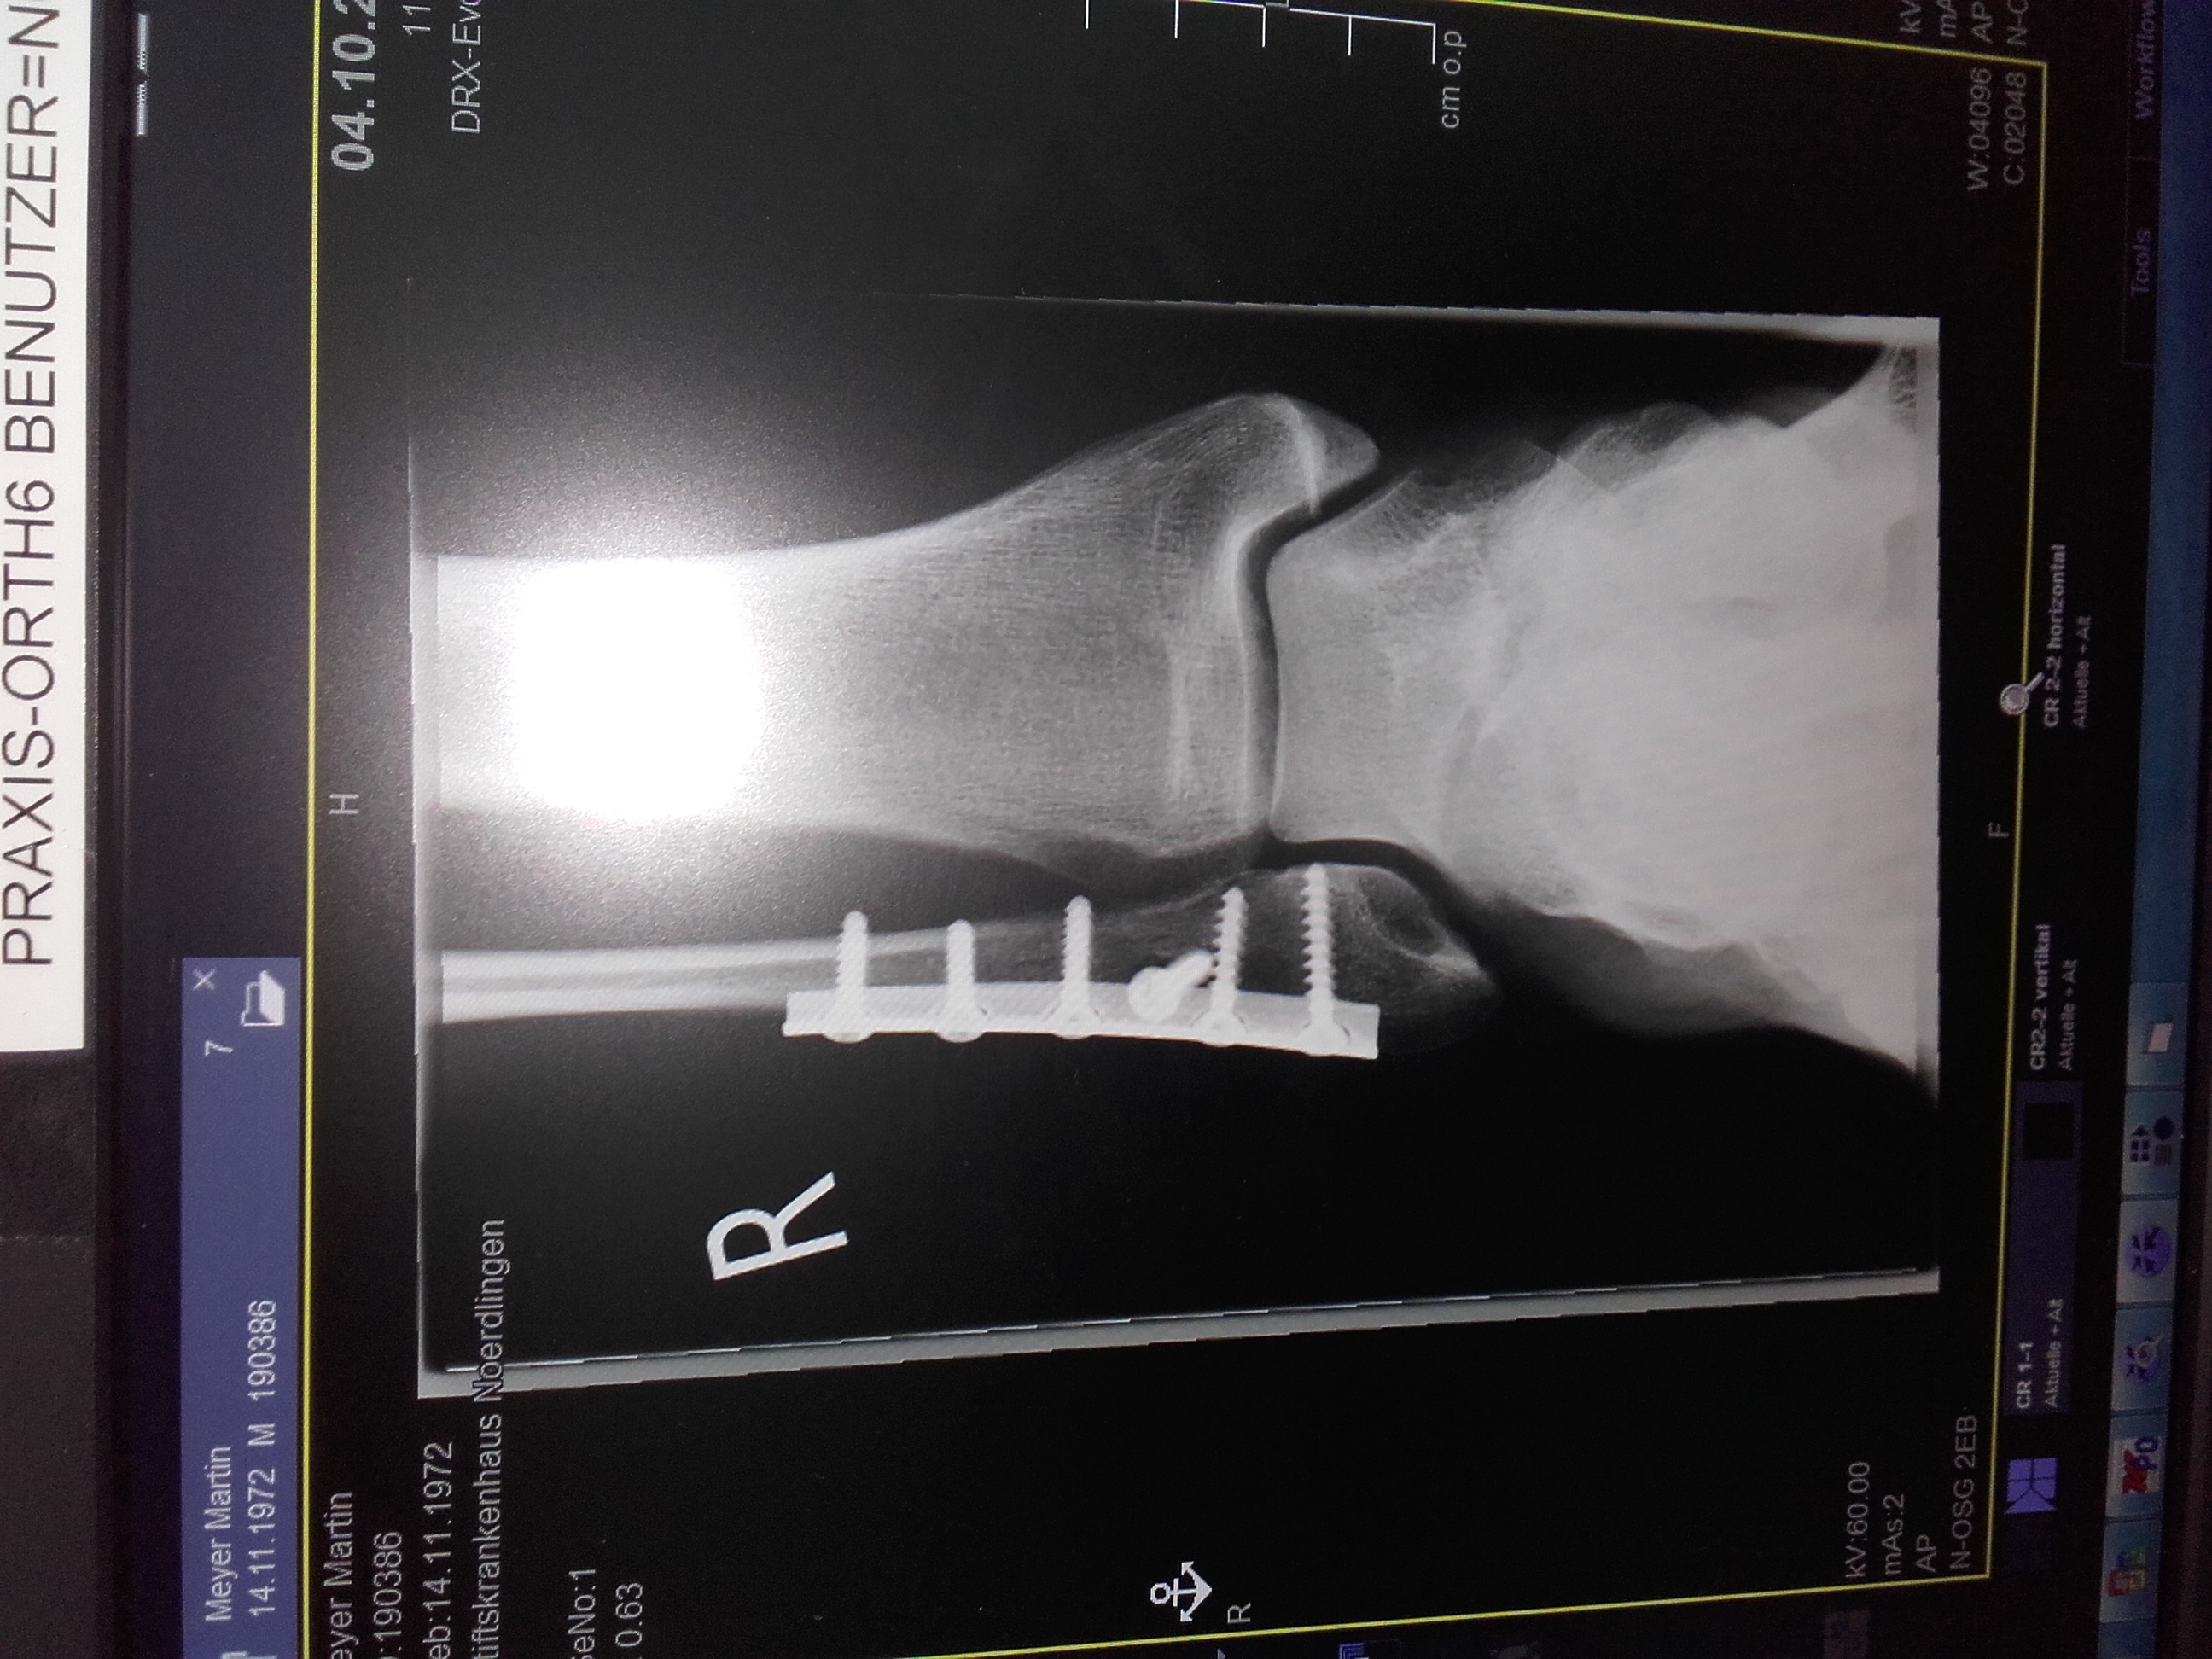

Iss ja niedlich , ich behalte meine Schrott drinne !!!!Dieses Bild ist GeschichteAnhang anzeigen 239457.

Gestern wurden die Schrauben entfernt und diese habe Ich soeben bekommen.